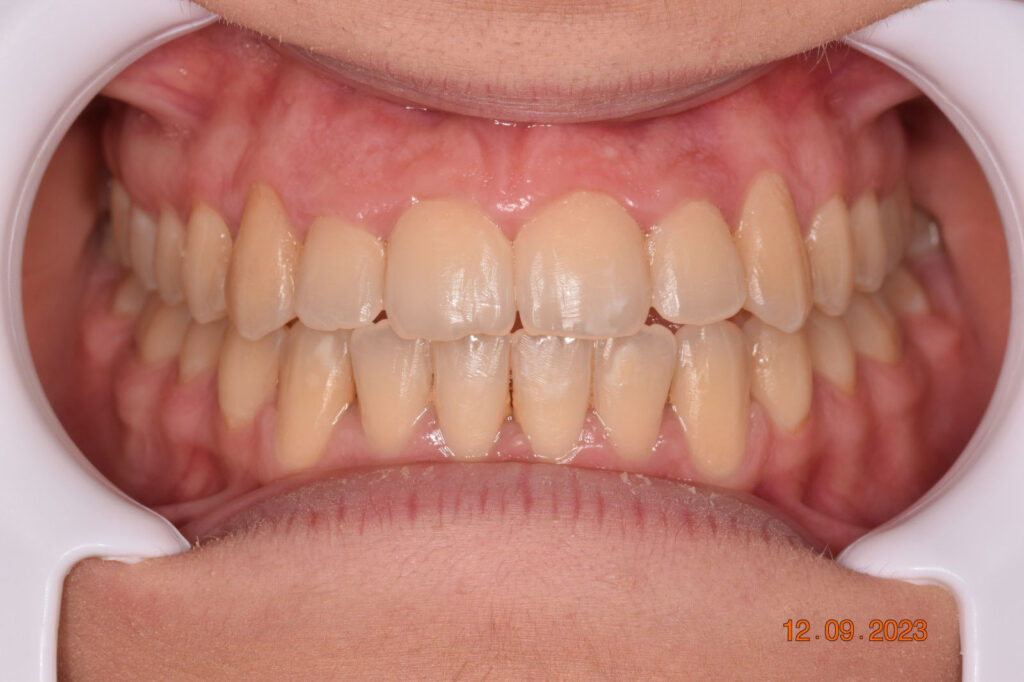

The teeth are in a very good position and the bone has reshaped.

This case posed challenges in all three spatial dimensions, compounded by significant crowding. The patient was highly compliant and maintained excellent oral hygiene throughout the 5.5 years of treatment, which required more than 30 clinical appointments.

The facial changes are impressive considering treatment involved only conventional orthodontics and not orthopedic interventions, TADs, or surgery.

Dr. Coca concludes that improved biomechanical understanding of extreme crowding and torque management could have reduced treatment duration. From his experience, proper force management can facilitate bone remodeling, challenging the idea of bone limitations in orthodontics.